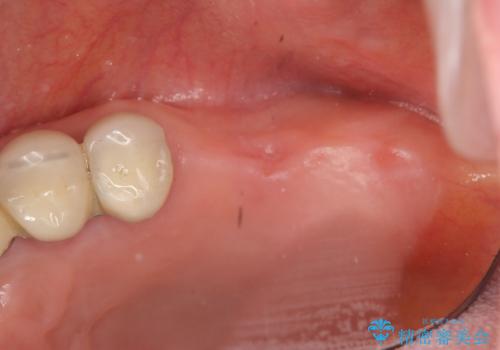

力学的に無理のある遊離端ブリッジをインプラントを用いて長期的な予後を見込める補綴状態へと改善しました。

- 外科手術のため、術後に痛みや腫れ、違和感を伴います